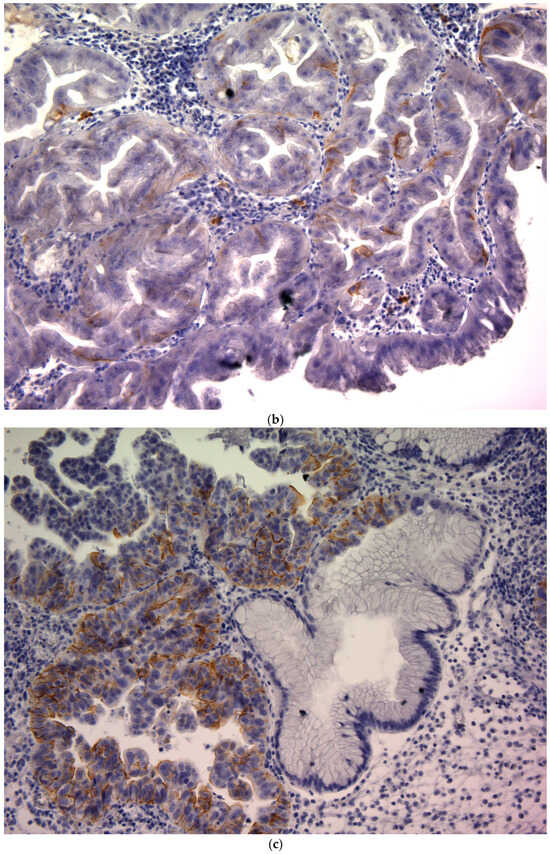

CD44v9 expression was evaluated by immunohistochemistry (IHC) using pretreatment endoscopic biopsy specimens. Biopsy tissue blocks that were fixed in formalin and embedded in paraffin were sliced into 2 μm thick sections, deparaffinized using xylene, and rehydrated through a series of ethanol solutions of increasing concentration. To reveal antigenic epitopes, the sections underwent antigen retrieval by autoclaving at 121 °C for 15 min. To prevent non-specific binding, the sections were treated with a diluted skim milk solution for 30 min at room temperature. Subsequently, they were exposed to a primary monoclonal antibody targeting CD44v9, which was developed in our laboratory, for 1 h at room temperature []. The antibody was diluted to approximately 0.1 μg/mL (~1:100) using an antibody-diluent (Thermo Fisher Scientific (Waltham, MA, USA)). After three washes with Tris-buffered saline (TBS), a secondary antibody was applied using the Histofine Simple Stain MAX PO detection system (Nichirei Biosciences Inc., Tokyo, Japan) for 30 min at room temperature. Subsequently, the sections were washed again with TBS, and the chromogenic reaction was developed using the Histofine DAB substrate kit (Nichirei Biosciences Inc.) for 4 min to visualize CD44v9 expression. Finally, the sections were counterstained with hematoxylin to stain the nuclei. Known CD44v9-positive gastric carcinoma tissues were used as positive controls, and staining with an isotype-matched irrelevant antibody was used as a negative control. Semi-quantitative scoring of CD44v9 immunoreactivity was performed by assessing the membranous staining intensity using a 0–3+ scoring system adapted from previously published criteria originally developed for CD44 IHC []. The intensity-based scoring guidelines were as follows: score 0 was assigned if there was negative or only weak membranous staining in <10% of tumor cells; score 1+, weak membranous staining in ≥10% of tumor cells or moderate intensity staining in <10% of cells; score 2+, moderate staining in ≥10% of tumor cells or strong (intense) staining in <10% of cells; and score 3+, intense membranous staining was observed in ≥10% of tumor cells (Figure 1). For each case, a consensus score (0, 1+, 2+, or 3+) was determined after reviewing any inter-observer differences (Figure 1). For analysis, CD44v9 expression was further categorized into low and high expressors: low CD44v9 expression was defined as an IHC score of 0, 1+, or 2+, whereas high CD44v9 expression was defined as a score of 3+. The evaluation of expression was conducted independently by two authors (K.S. and K.K.) under a blinded protocol, with the observers being unaware of the clinical outcomes and all other clinicopathological parameters of the patients.

Figure 1.

CD44v9 expression in gastric cancer cells as assessed by immunohistochemistry (×400). (a) Score 0: membranous staining in <10% of tumor cells; (b) Score 1+:weak membranous staining in ≥10% of tumor cells or moderate intensity staining in <10% of tumor cells; (c) Score 2+: moderate staining in ≥10% of tumor cells or strong (intense) staining in <10% of tumor cells; and (d) Score 3+: intense membranous staining is observed in ≥10% of tumor cells.